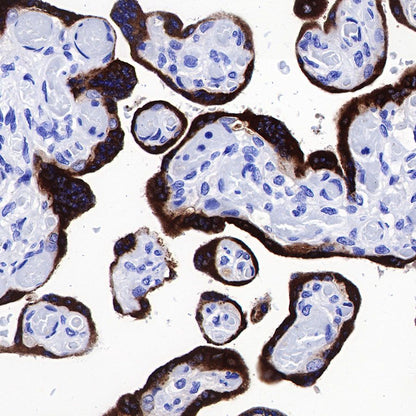

IHC shows positive staining in paraffin-embedded human placenta. Anti-CGB/HCG-β antibody was used at 1/1000 dilution, followed by a HRP Polymer for Mouse & Rabbit IgG (ready to use). Counterstained with hematoxylin. Heat mediated antigen retrieval with Tris/EDTA buffer pH9.0 was performed before commencing with IHC staining protocol.